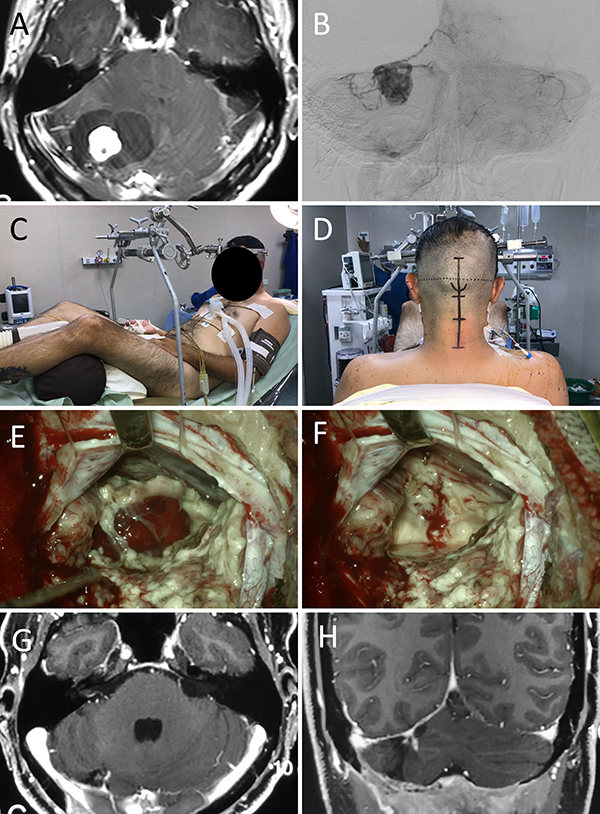

Figura 9:

Hemangioblastoma de fosa posterior A: RM preoperatoria; B: Angiografía digital preoperatoria; C-D: Posición; E-F: Hallazgos intraoperatorios.